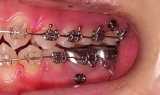

歯科矯正用アンカースクリュー

.

固定源の強化のために使用する小型のインプラントで,純チタンのミニスクリューです.

直径1.5mm程度のセルフタッピングスクリューを必要に応じて設置しています.粘膜切開の必要はありません.